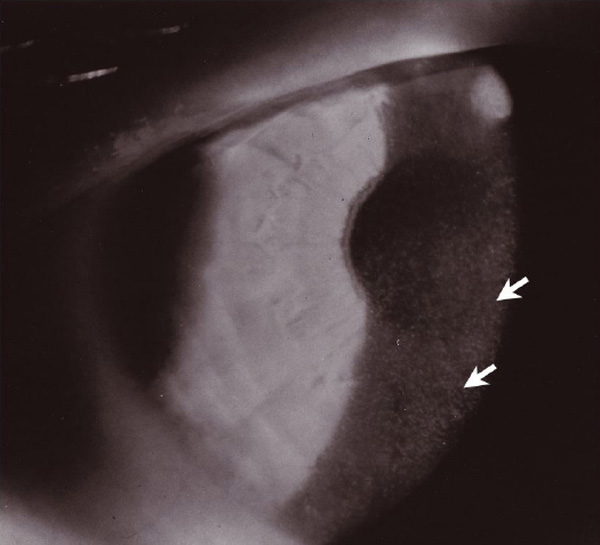

Figure 2. Slit-lamp photograph demonstrating discrete microcysts in the anterior corneal epithelium

Microcysts ranged from clear vesicles to opacified inclusions.